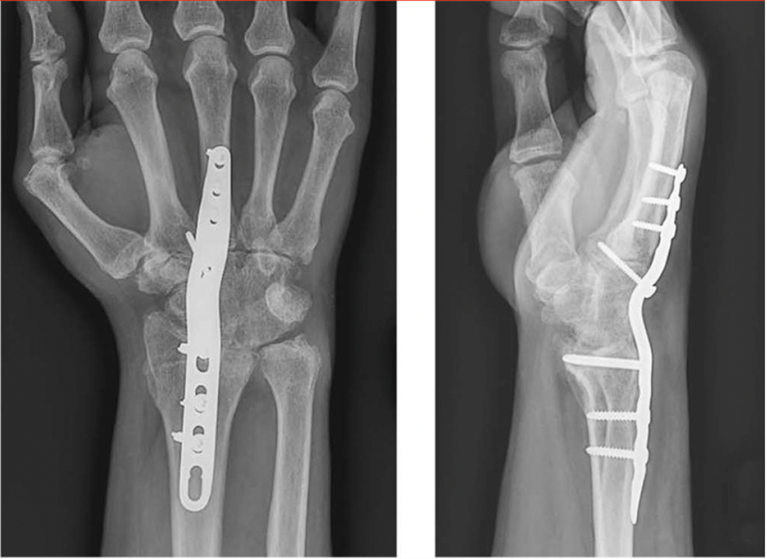

• The surgeon then performs final fixation of the fusion site. This can be done with wires, screws, staples, plates, etc. For a complete fusion of the whole wrist, a robust plate with screws is often used. The surgeon often uses X-rays during the procedure to ensure correct alignment of the joint and placement of the hardware.

X-rays Showing Wrist Post-Fusion

X-rays of the patient from Figure 1 after their wrist fusion surgery. A plate with screws has been applied across the wrist joint to hold it in the desired alignment while the fusion site heals.

Adapted with permission from Wei DH, Feldon P. Total Wrist Arthrodesis: Indications and Clinical Outcomes. J Am Acad Orthop Surg. 2017;25(1):3-11. doi:10.5435/JAAOS-D-15-00424